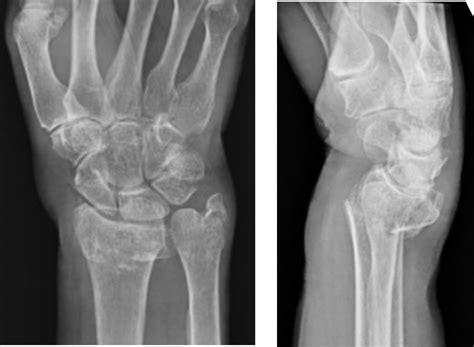

• Imaging Tests: X-rays are the primary imaging test used to diagnose wrist fractures. They provide detailed images of the bones and can help identify the location and severity of the fracture.

In some cases, additional imaging tests such as CT scans or MRIs may be required to get a more detailed view of the fracture, especially if the X-ray results are inconclusive or if there is suspicion of soft tissue damage.